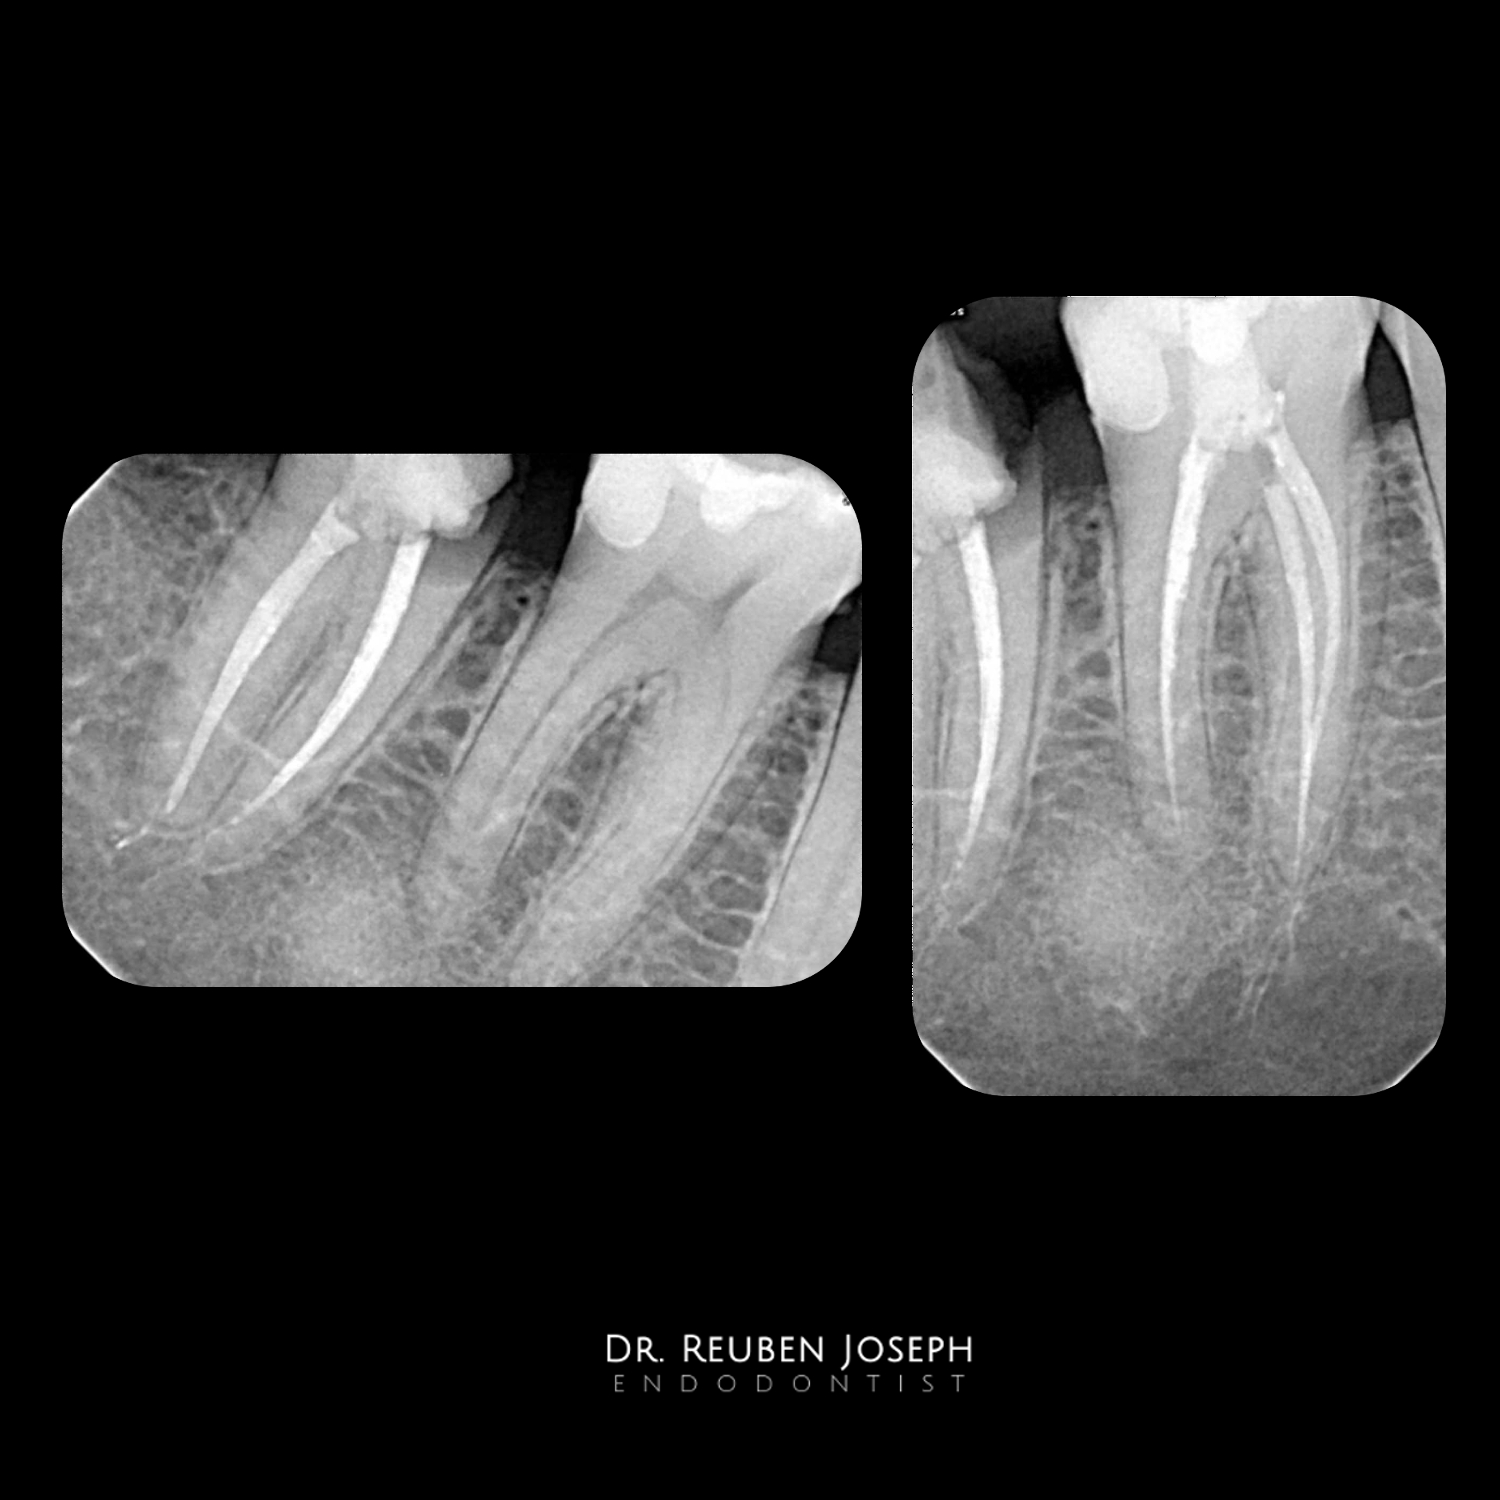

#37 RCT done in 2 visits

[post-views]